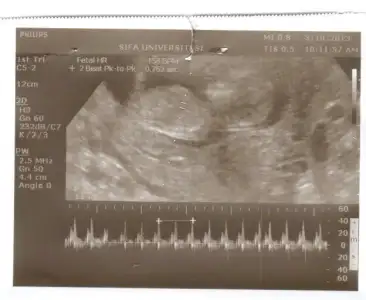

burda 11hafta 6 günlük dayanamadım gittim. eşim hemen cinsiyeti sordu.dr a.dr dikişlerimden sezeryan olduğumu anladı ilk çocuğu sordu kız deyince kıyafetlerini attınız mı dedi hayır dedik bu da kız dedi.yani kız gibi görünüyo.dedi..pipisi çok küçükse onu bilemem.ama 15 gün sonra gelin daha kesin konuşurum dedi...

eşimin halini sormayın bir bozuldu bir bozuldu..diyor ben 3.istiyorum.ben de erkek çocuğun garantisi var mı dedim.dedi kız da olsa başka istemem.kaderim der dururum..çalışıyorum ne yapıcam ben?..yani, sevincim kursağımda kaldı.araba almıştım onun taksitlerini ödüyordum onu bile verirdim o sevinçle sen işini bilmiyorsun diyor ya..arkadaşlar ne yapayım ben..maske de takamam mutluyum işte 2.prensesim gelir inşallah Allah ın izniyle..

canim dr un kiz demis ama ilki kiz gibi ikinci resimm ise bariz erkekk